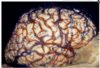

10

Q

A 4-year-old male presents with new onset headaches, nausea, and vomiting and is found to have a posterior fossa tumor. The tumor

is resected and the histopathologic specimen is shown (figure 1). Which of the following is the most likely diagnosis?

O Pilocytic astrocytoma

O Glioblastoma multiforme

o Pilomyxoid astrocytoma

Ependymoma

O Medulloblastoma

A

Medulloblastoma